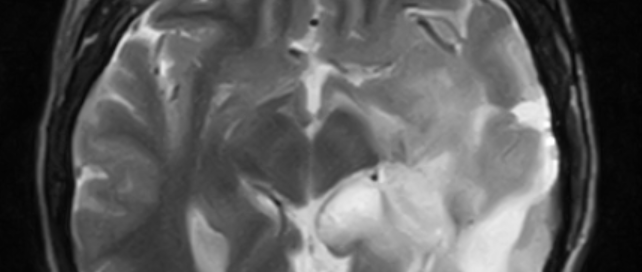

MRI Timeline

How Many So Far? I’ve taken probably 39 MRI scans since 2006. Almost all of these tests were contrasted until I discovered that making so many MRI scans with gadolinium-based contrast was a bad decision. Therefore, in early 2018, I began to omit part of the contrast with each MRI until I was told that